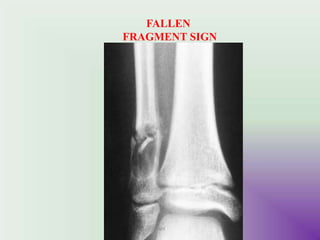

FALLEN FRAGMENT SIGN - # fragment in the cyst

FALLEN

FRAGMENT SIGN

Bone cyst of

humerus

Pathologic fracture

“Falling Fragment Sign”

- Cysts progressfrom active to quiescent to involutional stage . - cysts usually shrink as patient approaches skeletal maturity. - Radiographic features : metaphysis of immature skeleton , DIGNOSTIC- well marginated , centrally located ,purely lytic lesion. radiolucent that expand and thin the cortex . FALLEN FRAGMENT SIGN - # fragment in the cyst DD : ABC & fibrous dysplasia UMY

Bone cyst of humerus Pathologicfracture “Falling Fragment Sign” UMY